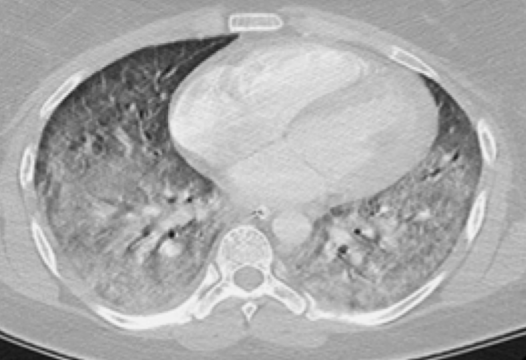

Acute respiratory distress syndrome

- normal heart

-no pleural effusion

-bilateral widespread pulmoonary inflitrates

-air bronchograms